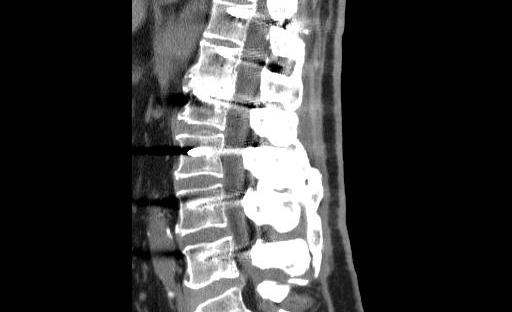

Dal lettino alla divisa: la mia doppia storia di paziente e terapista dopo un’artrodesi lombare

Tre anni fa mi sono ritrovato dall’altra parte del lettino. Dopo anni di sport, cadute importanti sullo snowboard e una predisposizione genetica che non ha mai giocato a mio favore, il mal di schiena era diventato un compagno di viaggio costante. Quando la qualità della vita ha iniziato a risentirne davvero, ho deciso di affidarmi… Continua a leggere Dal lettino alla divisa: la mia doppia storia di paziente e terapista dopo un’artrodesi lombare

la microchirurgia per la colonna vertebrale… come la facciamo noi!

Dopo aver sedimentato gli elementi degli articoli precedenti, proviamo a spingerci un passo oltre... come facciamo noi! Vogliamo quindi rendere i nostri interventi più sicuri -interventi che sono necessari se ravvisiamo che una malattia ormai "è lì per restare" e non guarirà da sola. Il modo migliore per ridurre il rischio di far del male… Continua a leggere la microchirurgia per la colonna vertebrale… come la facciamo noi!